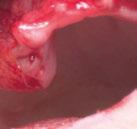

dentarias, cumpliendo parámetros biológicos, terapéuticos, mecánicos y estéticos. Después se realizó un modelado digital retrospectivo (Figuras 7-11) para generar modelos impresos 3D para realizar el mock up funcional, estético y como guía para las preparaciones (Figuras 12-15). Con ello, se efectuaron las preparaciones dentarias y los registros intermaxilares y, posteriormente, se digitalizaron ambos maxilares (Figuras 16-21)

En las piezas 16 y 17 el paciente presentaba restauraciones atornilladas de metalcerámica sobre implantes oseointegrados. Se planificó realizar estas en una fase posterior a la rehabilitación de las piezas dentarias mediante flujo digital con bases de titanio y cuerpos de escaneo.

Finalmente, las restauraciones se cementaron adhesivamente (Figuras 31-35). En las piezas 16 y 17 se realizaron restauraciones cementoatornilladas como última fase de tratamiento. Se recomendó al paciente una férula de protección superior la cual fue elaborada mediante un flujo de trabajo digital (Figura 36)